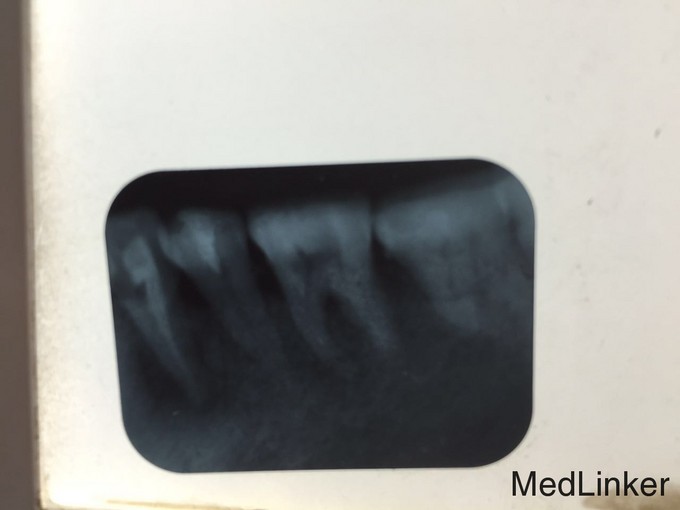

主诉:左上后牙疼痛一周余。 病史:左上后牙牙冠缺损一年余未治疗现疼痛明显夜间痛加重故前来就诊